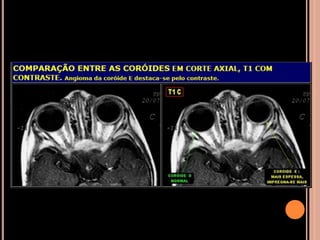

NF2

CALCIFICAÇÕES NÃO NEOPLÁSICAS DO PLEXO

CORIÓIDE

VL, assimétrica ou unilateral;

Usualmente não apresenta crescimento em exames

seriados;

TC